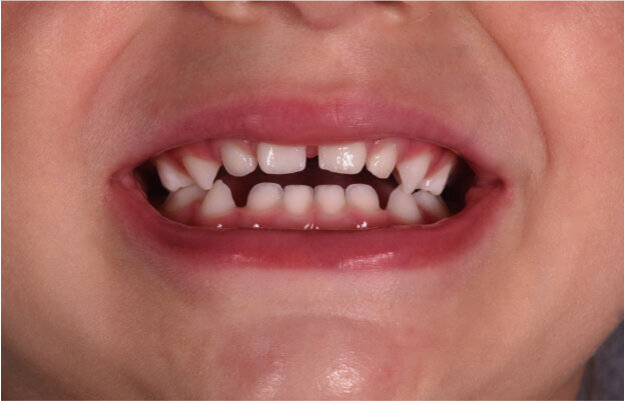

Caso 2 Paziente di anni 4, malocclusione dentale di III Classe, morso crociato monolaterale dx. La paziente viene trattata con dispositivo Amcop TC 2, il quale indossato tutte le notti e 1 ora di pomeriggio in 8 mesi risolve la malocclusione ripristinando il corretto rapporto occlusale; durante la terapia si riscontra un netto miglioramento della respirazione nasale e quindi il ripristino delle normali funzioni respiratorie. Il dispositivo, nei mesi successivi, viene indossato dalla paziente solo la notte per stabilizzare il caso e per guidare la crescita nel miglior modo possibile; all’età di 6 anni la paziente viene sottoposta a check-up ortodontico completo e quindi a panoramica e teleradiografia per poter analizzare anche la previsione di crescita e stabilire un eventuale step elastodontico (Figg. 15-23).

Fig. 15

Fig. 16

Fig. 17

Fig. 18

Fig. 19

Fig. 20

Fig. 21

Fig. 22

Fig. 23